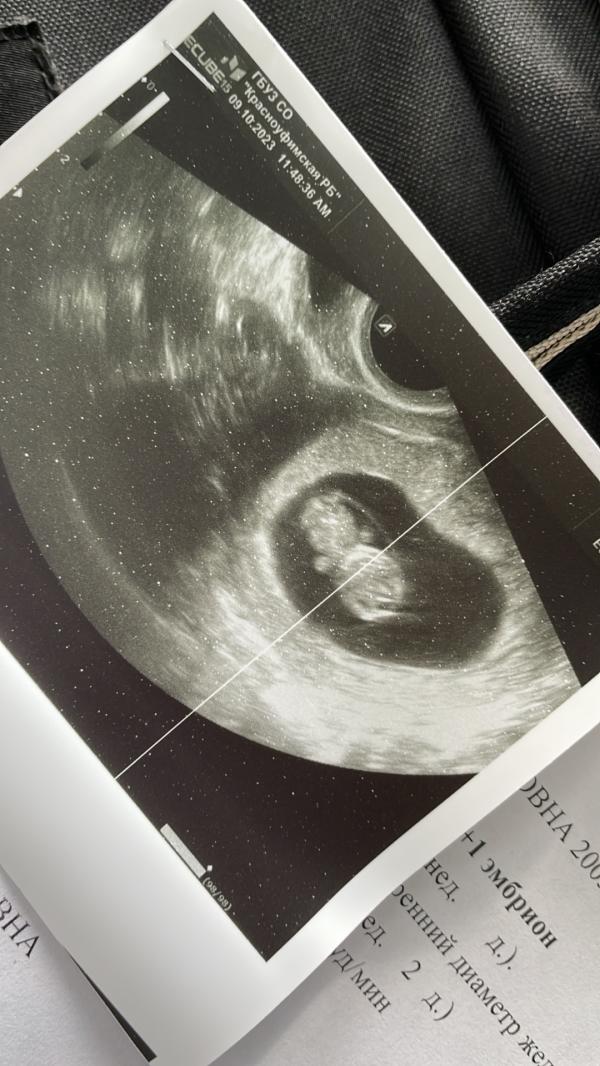

Первое УЗИ: что увидели, как прошло обследование, сколько ждать результатов и когда повторить?

Сегодня было первое узи!

09.10.2023